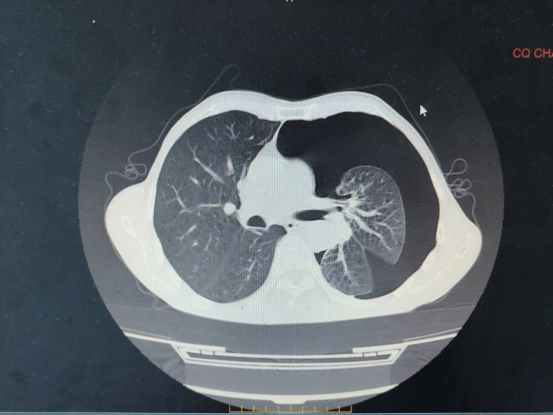

近日,区中医院收治“第3次肺大疱破裂、呼吸困难”患者,入院后,胸部CT提示:左肺多发肺大疱、气胸,左肺压缩约70%。区中医院外科团队仔细评估、精心准备,在肺病科、重症医学科、麻醉科的大力配合下,成功开展首例胸腔镜下左肺大疱楔形切除+胸膜粘连烙断+胸膜固定术,术后患者恢复良好,顺利出院。

术前